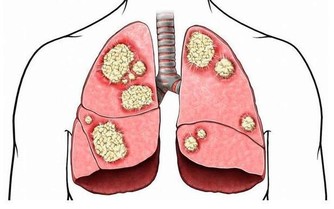

淋巴細胞也是白細胞的一種,能夠抵抗感染。如果淋巴細胞發生癌變,那麼會誘發淋巴瘤。血液科專家表示,淋巴瘤患者體內的淋巴細胞會發現許多變化,例如分裂方式不同於健康細胞,或者是在應該死亡時依舊活躍在患者體內,無法代謝。